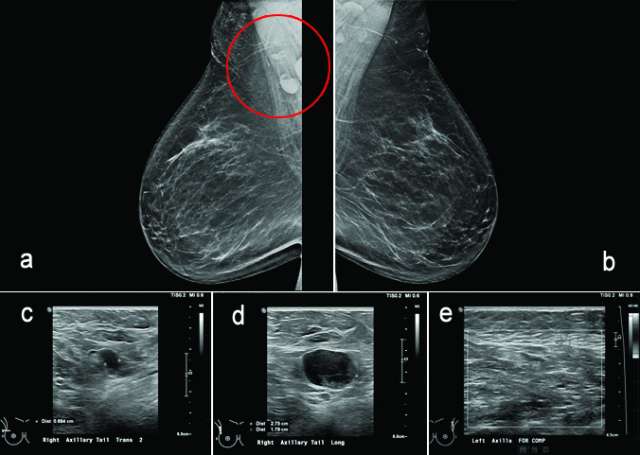

Figure 6, a-e.

The axilla is partially imaging during mammography and axillary lymph nodes are commonly seen. Evaluation of lymph nodes on mammography involves assessment of laterality and lymph node morphology. Benign axillary lymph nodes (figure 1) are oval in shape, typically measuring less than 2 cm, with a preserved fatty hilum which appears as radiolucent notch on mammogram. Increased lymph node size or density can be abnormal, requiring additional evaluation1. In the case of abnormal lymphadenopathy, attention should be made to whether the lymph nodes are unilateral or bilateral as this can help narrow the differential diagnosis1,2.

Ultrasound is the best modality for characterizing lymph nodes allowing for evaluation of shape, cortical thickness and presence or absence of fatty hilum. On ultrasound, normal axillary lymph nodes have an oval or lobulated shape with a preserved fatty hilum and cortical thickness less than 3 mm (figure 2). The echogenic hilum has arterial flow which can be assessed using color doppler imaging.

Features concerning for malignancy include round shape, increased cortical thickness and loss of fatty hilum1. The relationship of the lymph node cortex to hilum can be used to classify lymph node morphology and likelihood of malignancy. As the cortical thickness increases, there are reciprocal changes in the hilum beginning with hilar effacement and progressing to absence or replacement of the lymph node hilum2,3. Cortical thickening (figure 3) is considered the earliest morphologic change associated with malignancy; however, this finding is nonspecific with a low positive predictive value1-3. Absent/replaced hilum (figure 4) is the most specific for malignancy with a positive predictive value of 58-97%2.